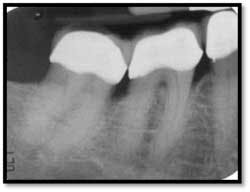

Severe bone loss #26, 8mm DF, 5mm straight facial, +2 mobility

Pockets 4-7mm Possible periapical abscess #15

LL Pre TxPC 4-12mm, Class lll buccal and lingual furcation

Possible endodontic abscess #18